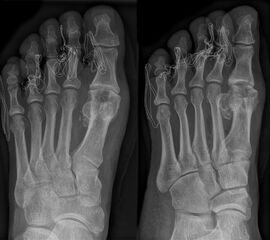

• Röntgen: Fuß belastet in 3 Ebenen.

• Optional MRT und CT bei radiologisch unklaren Verhältnissen.

Zum Lesen der Bildbeschreibung und zur Vollansicht bitte das Bild anklicken (Foto: M. Walther).